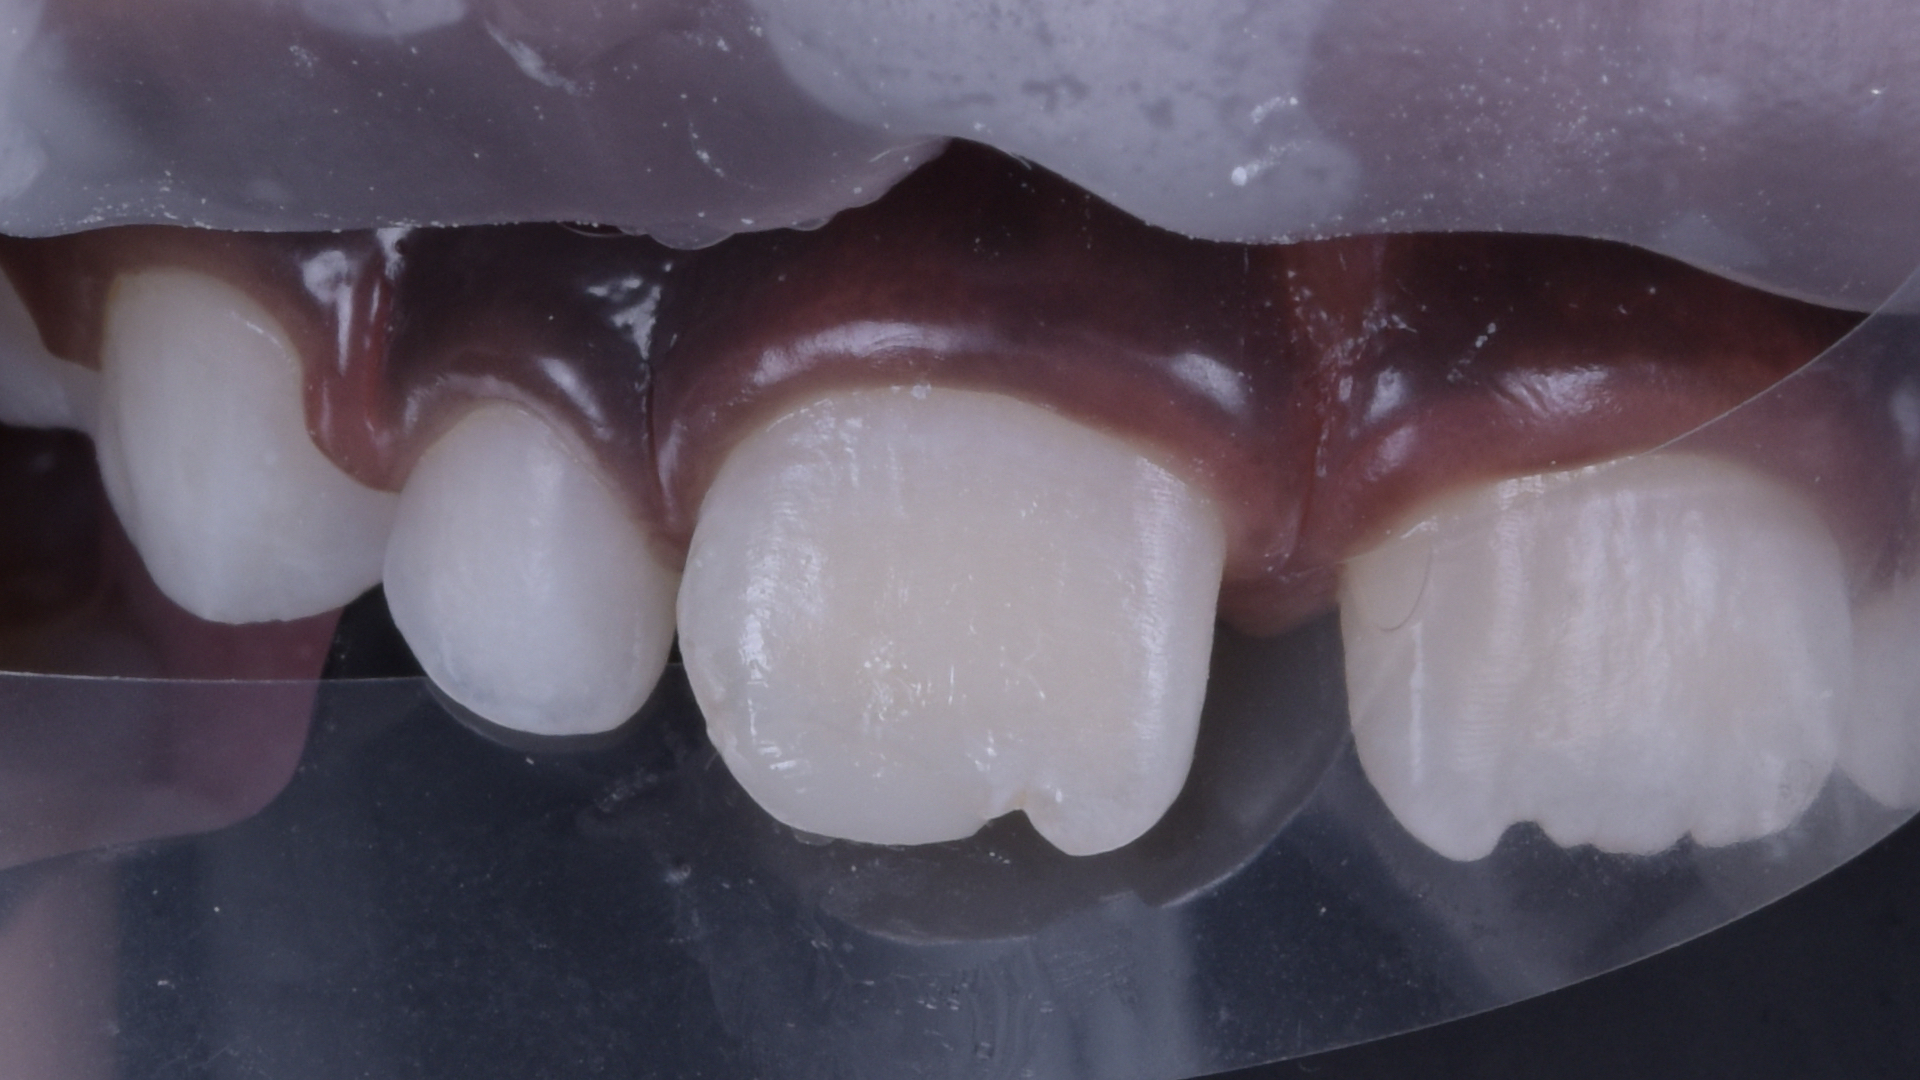

Finger Index Technique.

Ein Finger dient als Grundlage für die Applikation von 3M Filtek Easy Match Universal Komposit im Farbton Bright zur Wiederherstellung der Form, Kontur und Ästhetik.

Restauration mit Komposit.

Freihand-Modellation der Komposit-Restauration.